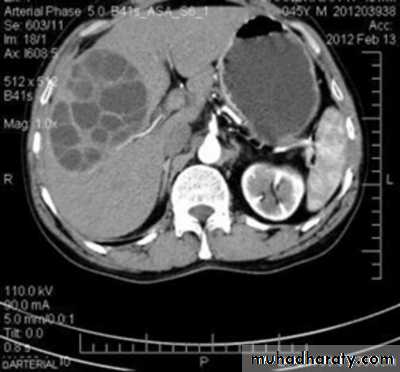

Hydatid cyst

Appear as large oval hypo dense area density of fluid with well defined margin , sometime at their periphery multiple flecks of calcification are seen at their periphery .

Hydatid cyst with daughter cyst , appear as multiple hypo densities rounded area within the main loculi with multiple rim of

calcification

Hydatid cyst within the liver

CT Scane